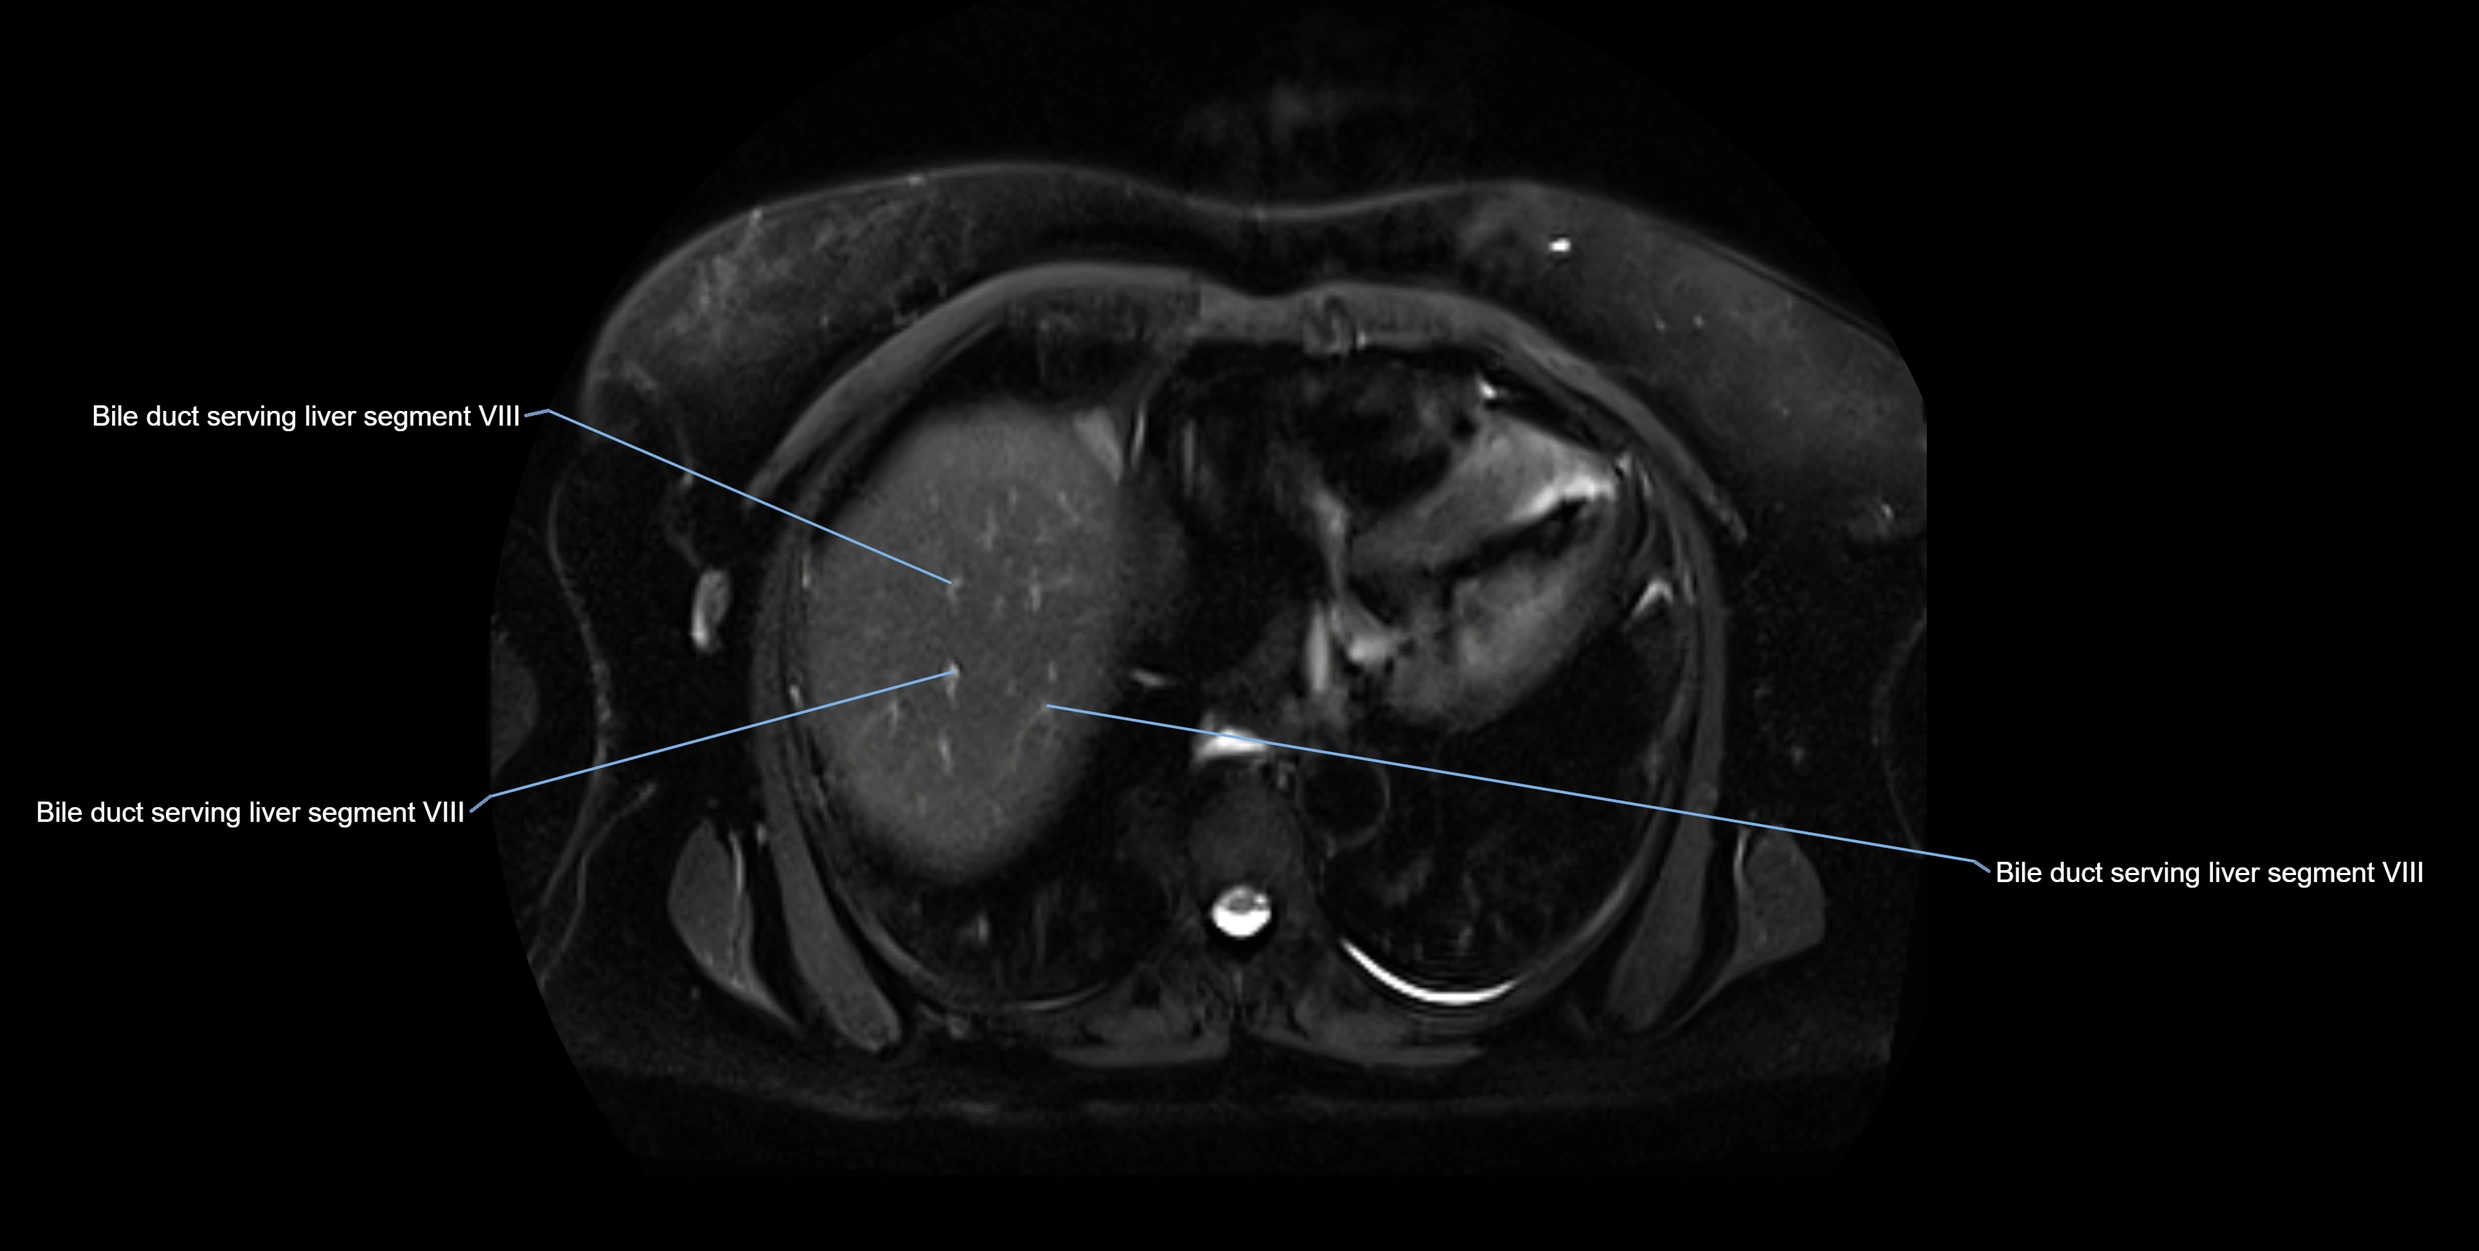

MRI image

image